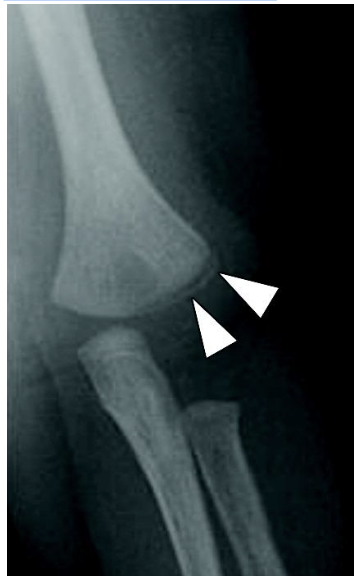

Metaphyseal Fractures

These are also known as bucket handle/corner fractures. These are the most SPECIFIC and PATHOGNOMONIC for nonaccidental trauma. This type of injury often occurs as microfractures from whiplash/shearing forces. This often presents exclusively in children under 2 years old because they are small enough to be shaken and not enough muscle development has occurred to protect their own limbs. However, please check patient’s birth history! In newborns, this can be a finding that can occur after traumatic deliveries where the baby presents in the breech position.